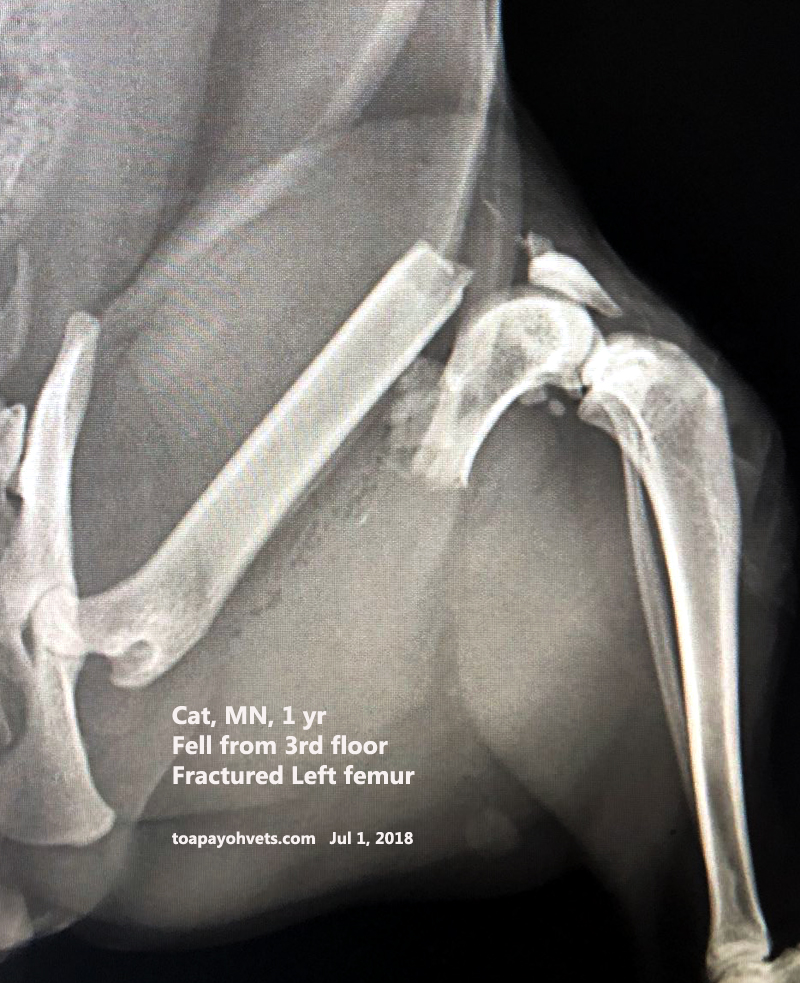

From 2010vets.blogspot.com

Veterinary, Photography and Travel Stories for vet students and pet Cat Hip Swollen Most cats with a hip dislocation will have severe hind limb lameness and may not be able to put any weight on the affected limb. It can affect one or all four of the cat’s legs. In this article, we look at some of the. Hip dysplasia is the medical term describing abnormal development of the hip joint. When a. Cat Hip Swollen.

Veterinary, Photography and Travel Stories for vet students and pet Cat Hip Swollen Hip dysplasia in cats is a genetically inherited malformation of the hip joint. Hip dysplasia refers to a malformation of the hip joint. Clinical signs of feline hip dysplasia include limping or other apparent difficulties in walking, avoidance of physical activity, expression of pain if the hip is touched, and persistent licking. In this article, we look at some of. Cat Hip Swollen.